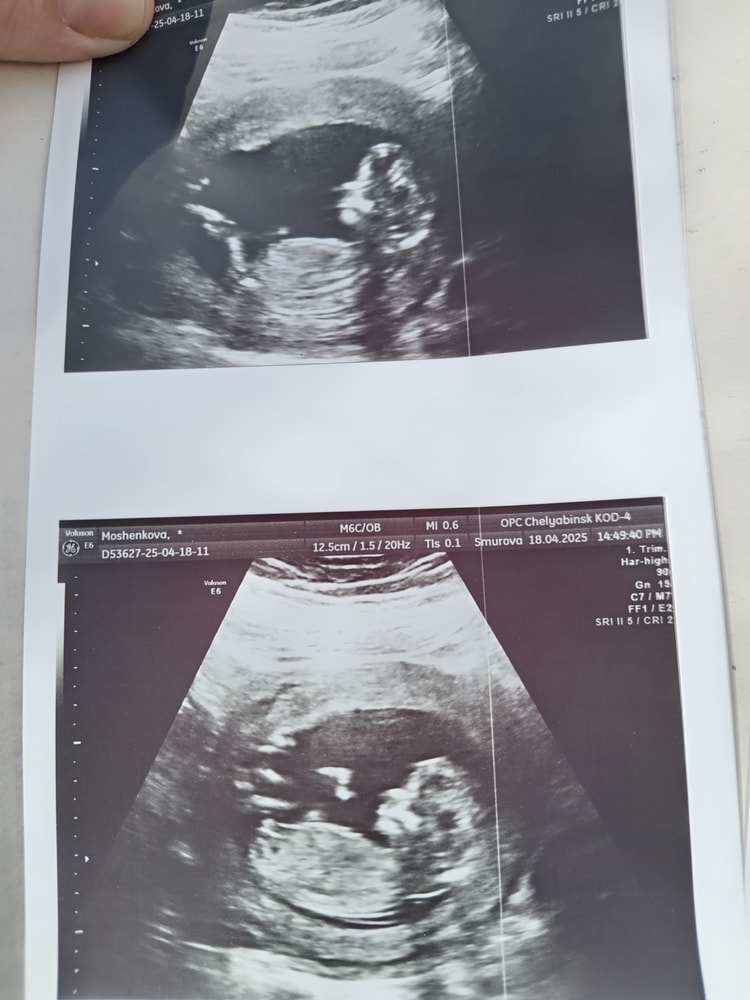

Оксана Мощенкова в Клуб беременных 8 месяцев Половой бугорок Пол малыша Девочки привет, как вы думаете кто будет, я что-то не пойму где тут половой бугорок😵💫😁 Посмотрите еще 20 записей на эту тему Отменить Ответить Елена Ивановская Вы узнали, кто у вас в итоге?) 16.05.2025 Ответить Оксана Мощенкова Елена Ивановская, нет ещё 16.05.2025 Ответить Мама дочи Плохо видно. Скорее всего девочка 20.04.2025 Ответить Юлянка Мальчик 20.04.2025 Ответить Оксана Мощенкова Юлянка, я поняла, что это половой бугорок 20.04.2025 Ответить Nika Какой носатенький мальчик😍 20.04.2025 Ответить Оксана Мощенкова Nika, это половой бугорок 20.04.2025 Ответить Оксана Мощенкова Оксана Мощенкова, 20.04.2025 Ответить Nika Оксана Мощенкова, я поняла))) 20.04.2025 Ответить Помогите определить пол ребёнка Пол малыша Чаты Беременных Выберите чат: Январята-2026 Февралята-2026 Мартята-2026 Апрелята-2026 Майчата-2026 Июнята-2026 Июлята-2026 Августята-2026